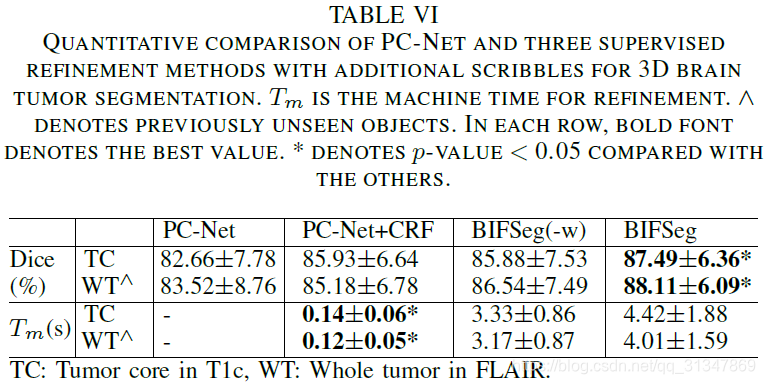

比较 BIFSeg 和 1)P-Net/PC-Net 的初始分割结果;2)用 CRF 处理之后的分割结果;3)BIFSeg(-w) 的分割结果(基于 Eq(1),所有像素的权重 w ( i ) = 1 w(i) = 1 w(i)=1),以及其他交互式分割方法:用于 2D 分割的 GrabCut,SlicSeg,Random Walks;用于 3D 分割的 GeoS,GrowCut,GrabCut 3D

2. 3D 图像分割

(3)Supervised Image-specific Fine-tuning: